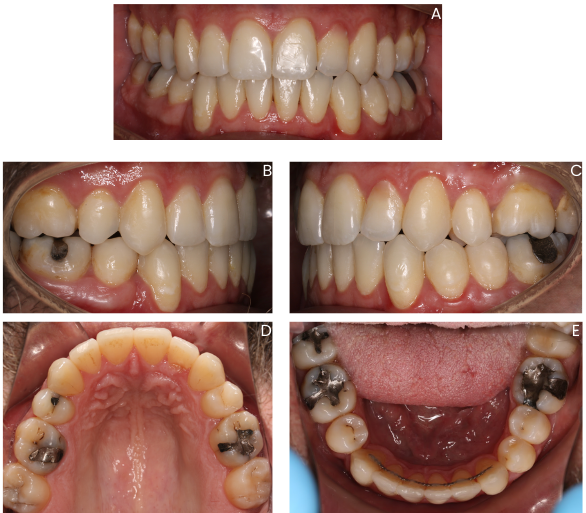

This is a case treated by the talented Dr. Salim Qadri using Eon Aligner. The patient was an adult male patient who presented with a Class III malocclusion requiring an extraction of the lower right first premolar followed by closure of the space. Dr. Qadri has requested to close that space using the SP9 protocol. As shown in figure 1 below, the before photos include the lower right first premolar, but it had been digitally extracted on the setup as requested by the doctor. The primary biomechanical concern for this case was the uncontrolled crown tipping during mesiodistal space closure.

As shown in the post-treatment photos in Figure 6, the primary treatment objective was successfully achieved. The extraction space was fully closed without undesirable distal tipping of the lower right canine or mesial tipping of the lower right second premolar into the space. Maintaining this level of control also contributed to improvement of the anteroposterior relationship on the right side and supported a more stable interdigitation overall.

Although this technique may result in a longer treatment time, the result reflects the impact of thoughtful staging and proper sequencing of movements, rather than relying on continuous, uncontrolled translation. It also underscores the role of well-designed attachments in facilitating controlled space closure and maintaining root position throughout treatment.